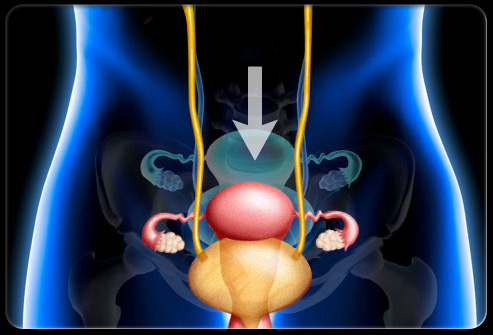

盆腔疼痛可能因为多种疾病或症状出现。比如,盆腔疼痛可能是单纯的痛经,也可能是阑尾炎或者膀胱问题,这些病症可好可坏,有些完全不是问题,有些则需要急救治疗。对于大多数人来说,如果出现盆腔疼痛的问题则需要去医院有专业人士进行检查。